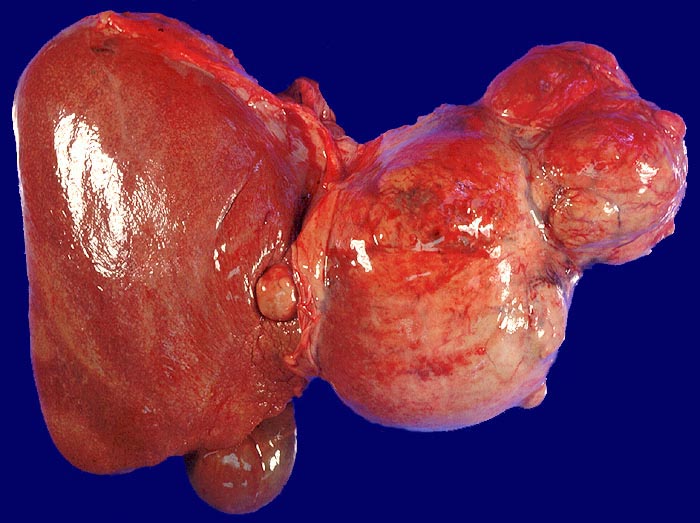

Makroskopisch imponiert das hepatozelluläre Karzinom als solitäre grosse Tumormasse, als zahlreiche zirrhoseartige Knoten oder als scharf begrenzter Knoten mit oder ohne Kapsel. Die tumorfreie Leber ist in der Mehrheit der Fälle zirrhotisch umgebaut. Mikroskopisch bilden die Tumorzellen mehr als 2 Zellen breite Trabekel (> 1237), kompakte Tumormassen (> 1229) oder pseudoglanduläre Strukturen (dilatierte Canaliculi) (> 1212) (> 1199). Desmoplastisches Bindegewebe fehlt meist. Innerhalb des Tumors fehlen Portalfelder. Es finden sich lediglich Arterien. Etwa bei der Hälfte der Karzinome lässt sich intrazytoplasmatische oder intracanaliculäre Galle (> 1238) nachweisen. Immunhistochemisch lassen sich mit einem polyklonalen Antikörper gegen Carcinoembryonales Antigen (CEA) Gallecanaliculi zwischen den Tumorzellen nachweisen. Die Tumorzellen bilden keinen Schleim.

• Scharf begrenzter bekapselter Tumor.